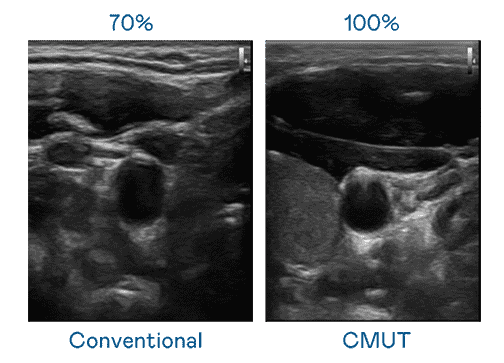

CMUT 技术是一种用电容式微机电元件来产生超音波讯号的技术。。。。与传统 PZT 压电式技术相比,,,CMUT 频宽增加 30%,,更宽频的超音波讯号让影像解析度大幅提升,,,是实现高影像品质医疗超音波扫描、、、、促进精准医疗发展的关键技术。。

大频宽带来超清晰影像

超音波影像的解析度高低,,,,首先取决于探头能发出的讯号频宽。。。尊龙集团 CMUT 可提供高清晰的超音波讯号,,,提供高频宽、、高灵敏度、、、、影像纹理细节更高的超音波影像,,协助医护人员缩短影像判读时间及利用精准的医疗影像进行诊断。。。